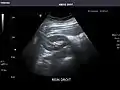

Abdominal Ultrasound (Full Exam)

STRUCTURED REPORT

(Technique: Transabdominal ultrasonography; Device: Toshiba Aplio XG)

Liver: Diffusely homogeneous and normal in echogenicity. No focal mass or contour nodularity. No intrahepatic biliary ductal dilatation.

Portal Vein: Patent main portal vein.

Gallbladder: No stones, wall thickening, or pericholecystic fluid.

Common Bile Duct: Nondilated measuring 1.3 mm at the level of the porta hepatis.

Pancreas: Visualized portions unremarkable.

Spleen: Normal in size.

Kidneys: Right and left kidneys measure 11.5 cm and 12 cm in length respectively. No hydronephrosis. Small left lower pole kidney cyst.

Ascites: None.

Aorta: Visualized portions normal in caliber, 16 x 15 mm.

IVC: Normal.

IMPRESSION:

Normal abdominal ultrasound.